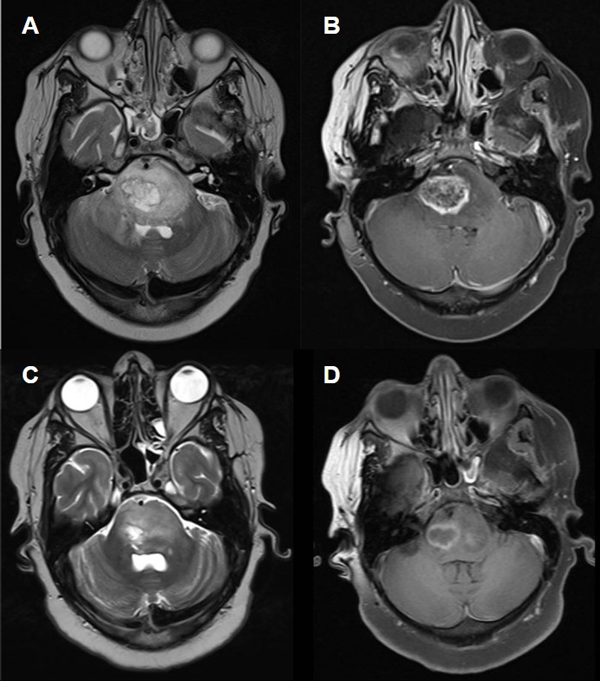

Se colocó una válvula de derivación ventrículo peritoneal previo a la intervención quirúrgica. Posteriormente se realizó la biopsia quirúrgica a cielo abierto mediante un abordaje subtemporal, de la cual se enviaron a patología 3 fragmentos de 2 cm x 1 cm. La anatomía patológica informó glioma difuso de línea media H3 K27M mutado (grado 4 de la OMS). (Fig. 1B-E). El paciente cursó 3 días de internación en unidad de terapia intensiva y 2 días en sala general, donde fue otorgado el egreso sanatorial por buena evolución. No presentó complicaciones ni intercurrencias. Actualmente se encuentra realizando tratamiento oncológico dirigido. (Fig. 2)

Fig 2: Caso 1: Imágenes de RMN postoperatoria, secuencias T2 y T1 con contraste (A y B 3 meses postoperatorios, C y D 8 meses).